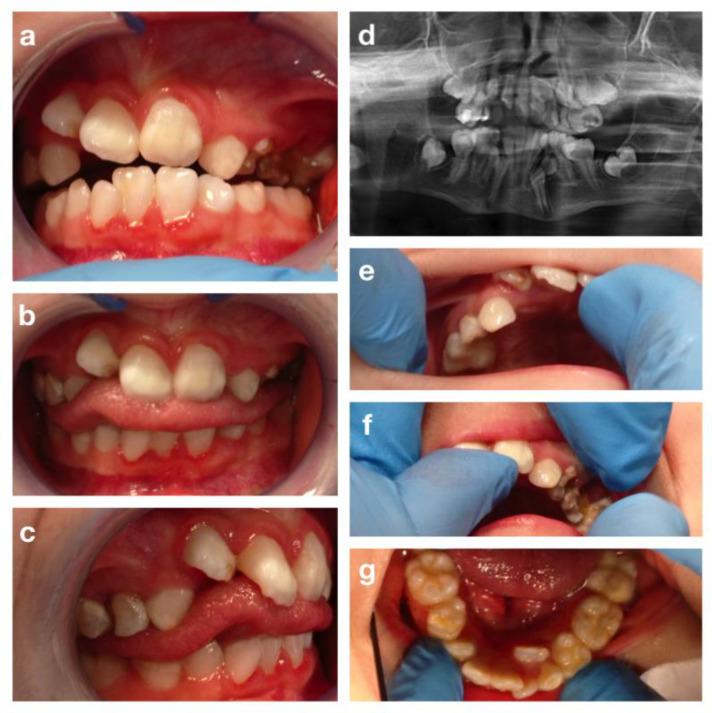

Rare genetic syndromes, conditions with a global average prevalence of 40 cases/100,000 people, are associated with anatomical, physiological, and neurological anomalies that may affect different body districts, including the oral district. So far, no classification of oral abnormalities in rare genetic syndromes is present in the literature. The aim of this narrative review is to analyze literature on rare genetic syndromes affecting dento-oro-maxillofacial structures (teeth, maxillary bones, oral soft tissues, or mixed) and to propose a classification according to the detected oral abnormalities. In addition, five significant cases of rare genetic syndromes are presented. The Scale for the Assessment of Narrative Review Articles (SANRA) was followed for this review. From 674 papers obtained through PubMed search, 351 were selected. Sixty-two rare genetic syndromes involving oral manifestations were found and classified. The proposed classification aims to help the clinician to easily understand which dento-oro-maxillofacial findings might be expected in the presence of each rare genetic syndrome. This immediate framework may both help in the diagnosis of dento-oro-maxillofacial anomalies related to the underlying pathology as well as facilitate the drafting of treatment plans with the involvement of a multidisciplinary team.